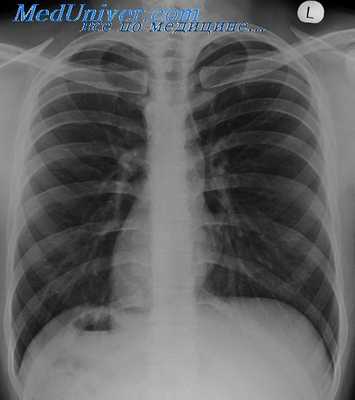

На рентгенограммах в прямой проекции на левом контуре сердца определяются две дуги: верхняя представлена часто наблюдающейся левосторонней дугой аорты и участком нисходящего отдела аорты, нижняя образована выходящим па левый контур ЛП. Дуга легочной артерии отсутствует. Правый контур сердца представляет собой сплошную выпуклую линию, простирающуюся от диафрагмы до основания сердца, которая образована вверху ПП и внизу ПЖ.

- Рентгенография ОГК. На рентгенограмме визуализируется смещение сердечной тени вправо, при комбинированных аномалиях изменяются контуры магистральных сосудов. Чтобы подтвердить транспозицию проводится рентгенография органов брюшной полости.